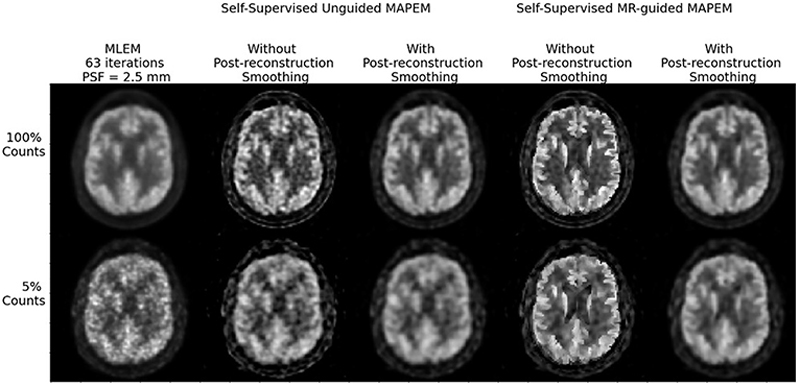

Reduced dose positron emission tomography (PET) lowers the radiation dose to patients and reduces costs. Lower-count data, however, degrades reconstructed image quality. Advanced reconstruction methods help mitigate image quality losses, but it is important to assess the resulting images from a clinical perspective. Two experienced clinicians assessed four PET reconstruction algorithms for [18F]FDG brain data, compared to a clinical standard reference (maximum-likelihood expectation-maximization (MLEM)), based on seven clinical image quality metrics: global quality rating, pattern recognition, diagnostic confidence (all on a scale of 0–4), sharpness, caudate-putamen separation (CP), noise, and contrast (on a scale between 0–2). The reconstruction methods assessed were a guided and unguided version of self-supervised maximum a posteriori EM (MAPEM) (where the guidance case used the patient’s MR image to control the smoothness penalty). For 3 of the 11 patient datasets reconstructed, post-smoothed versions of the MAPEM reconstruction were also considered, where the smoothing was with the point-spread-function used in the resolution modelling. Statistically significant improvements were observed in sharpness, CP, and contrast for self-supervised MR-guided MAPEM compared to MLEM. For example, MLEM scored between 1-1.1 out of 2 for sharpness, CP, and contrast, whereas self-supervised MR-guided MAPEM scored between 1.5-1.75. In addition to the clinical evaluation, pretrained convolutional neural networks (CNNs) were used to assess the image quality of a further 62 images. The CNNs demonstrated similar trends to the clinician, showing their potential as automated standalone observers. Both the clinical and CNN assessments suggest when using only 5% of the standard injected dose, self-supervised MR-guided MAPEM reconstruction matches the 100% MLEM case for overall performance. This makes the images far more clinically useful than standard MLEM.